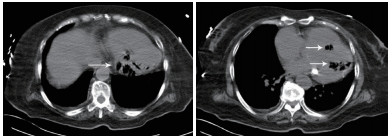

患者女性,75岁。因“被发现晕倒在地伴大小便失禁6 h余”于2018年10月25日12:10入院。患者为独居老人,当晚失联,入院6 h前,家人在家中发现其神志不清,大小便失禁,卧于床边,后患者家属呼120送至本院急诊科。入院后详细追问病史,患者身边无药瓶,家中亦无煤烟味。既往有“冠心病陈旧性心肌梗死、高血压病、2型糖尿病”病史11年余,“卵巢癌术后放化疗”病史2年余,“直肠占位”病史半年余。入院急诊体格检查:体温36.0℃,脉搏80次/min,呼吸17次/min,血压108/52 mmHg(1 mmHg=0.133 kPa),老年女性,神志不清,烦躁,面色苍白,皮肤湿冷、散在花斑,皮肤黏膜无破损。双侧瞳孔等大等圆,对光反射存在,言语、伸舌及肌力检查不合作,双肺呼吸音清,未闻及干湿性啰音,心率80次/min,律齐,心脏各瓣膜听诊区未闻及杂音,肝脾肋下未及,双下肢无水肿,四肢可见不自主活动,双侧病理征未引出。入院后心电图提示肢体导联及胸导联均有T波低平或倒置,V4-V6导联ST段压低(图 1)。血常规:白细胞计数32.35×109/L,中性粒细胞比率84.7%,中性粒细胞计数27.4×109/L,血红蛋白64 g/L,血小板计数221×109/L;CRP 111.9 mg/L,PCT > 100 ng/mL;肌酸激酶1 847 U/L,肌酸激酶同工酶356 U/L,肌酐219 μmol/L,肌钙蛋白T 6 257 pg/mL,NT-proBNP > 35 000 pg/mL。入院后急查颅脑、胸部及全腹CT,胸部CT提示左心室、室间隔及肺动脉根部区域见不规则条状、条片状低密度影,参考CT值约-200~-900 HU(气体密度影),外周伴伪影,左心室为著,外周分布为主,似累及心肌区域,部分心肌变薄,心包区域尚连续,主动脉系统未见气体影(图 2~3)。12:45患者病情急剧进展,呼吸心搏骤停,予气管插管、心肺复苏及药物抢救治疗,13:25抢救无效临床死亡,患者家属拒绝尸检。

| 图 1 患者入院心电图肢体导联及胸导联(均有T波低平或倒置,V4-V6导联ST段压低) |